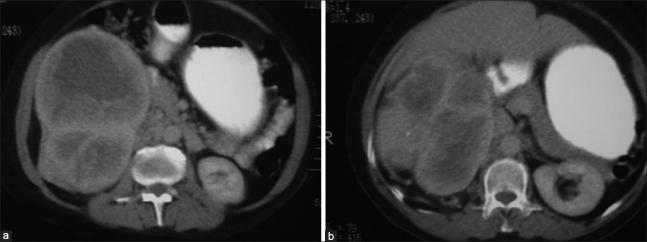

A case of solitary fibrous tumor of the kidney.

A solitary fibrous tumor (SFT) is an unusual spindle cell neoplasm that usually occurs in the pleura but has recently been described in diverse extrapleural sites. Urogenital localization is rare and to our knowledge, only 39 cases of SFT of the kidney have been described. Although SFT of the kidney is extremely rare, this tumor must be included in the differential diagnosis, whenever a renal tumor consisting of mesenchymal elements is encountered. We report a case of a large SFT of the right kidney which was clinically and radiologically thought to be renal cell carcinoma and a final diagnosis of SFT was made only after immunohistochemical study.

孤立性纤维瘤(SFT)是一种不常见的梭形细胞肿瘤,通常发生于胸膜,但最近也有在多种胸膜外部位的报道。泌尿生殖系统定位罕见,据我们所知,仅报道过39例肾孤立性纤维瘤。尽管肾孤立性纤维瘤极为罕见,但每当遇到由间充质成分构成的肾肿瘤时,该肿瘤都必须列入鉴别诊断。我们报告一例右肾巨大孤立性纤维瘤病例,临床和影像学检查均考虑为肾细胞癌,仅在免疫组化研究后才最终确诊为孤立性纤维瘤。